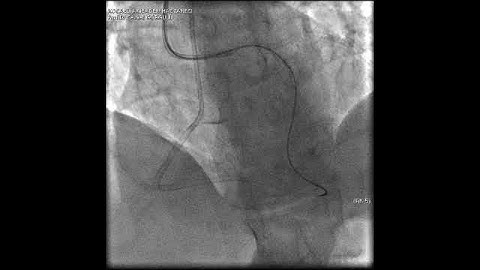

Aortic dissection and radial rupture during retrograde CTO PCI: Management of complications VİDEO 12